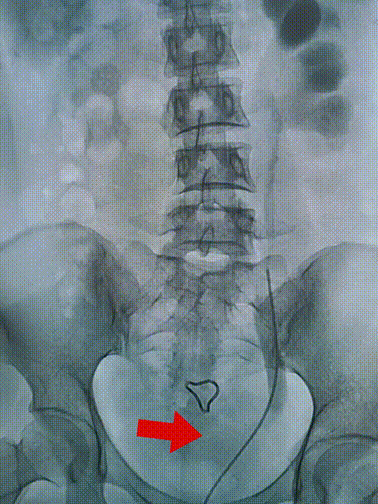

李女士术前造影检查